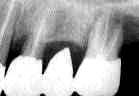

症例3

60歳・女性

術前3年6ヵ月

術直前(1985.7)

術直後

術後3年6ヵ月